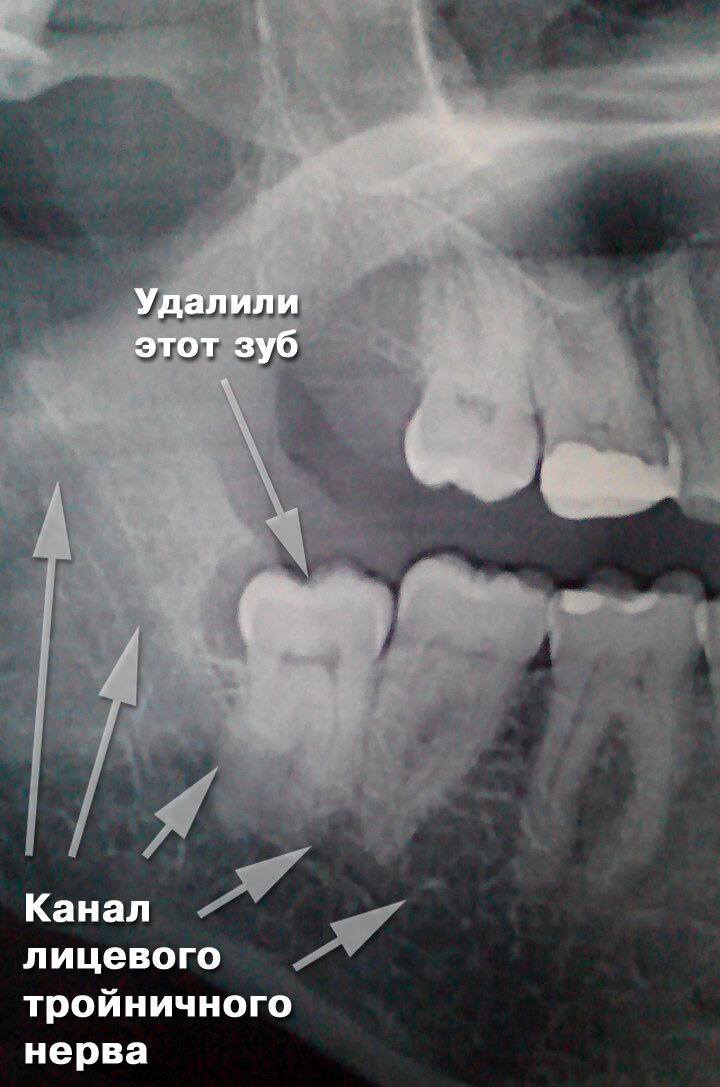

Доктор поставил анестезию, в том числе проводниковую, и сделал снимок, на котором он увидел два корня, переплетающихся между собой и частично вросшими в нервную ткань. Жаль фото рентгеновского снимка не Возможно сюда вставить.

А сидел зуб в челюсти примерно вот так:

Корнями прямо в нерве

В самом начале доктор вкатил мне анестезию и боль прошла. Мы сделали несколько рентгеновских снимков, чтобы убедиться, не осталось ли осколков зуба или может появилась трещина на челюстной кости. Но ни того, ни другого не оказалось, к счастью.

На снимке было отчётливо видно, как проходил нервный канал, будто ниточка, на которую насажены бусинки. И вот из этой гирлянды был удалён один компонент и цепь разорвалась, то есть теперь только ждать, когда отболит повреждённый участок. Доктор вытащил из лунки те штучки с лекарством и сгустком крови, которые почему-то не выпали. Прочистил там все, заложил новое лекарство и зашил дыру. Теперь от меня воняет этим медикаментом за версту просто и еда приобрела необычную нотку вкуса из-за него.